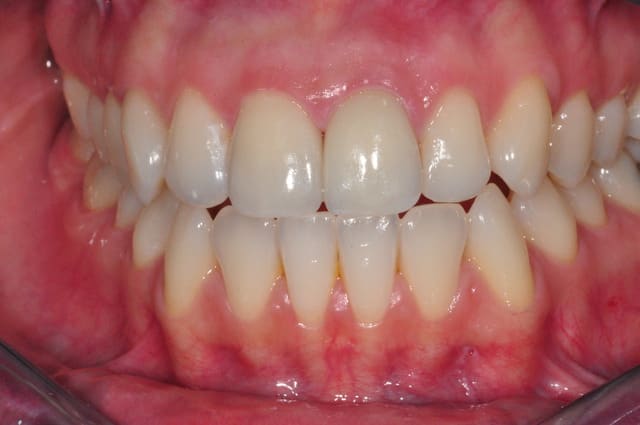

non en fait ma question porte sur l'état de surface de mes emax,

la coloration est présente depuis un bon moment et je n'en connais pas l'origine

je joins une photo avant traitement